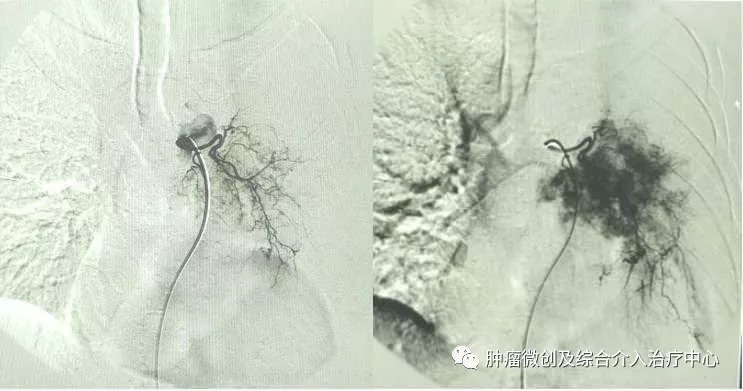

A:经支气管动脉灌注抗癌药物:有效提高肿瘤局部药物浓度,增强杀灭肿瘤细胞作用。用药量少,全身不良反应小。

经支气管动脉栓塞肿瘤供血动脉:可精确栓塞肿瘤供血动脉,促进肿瘤坏死。